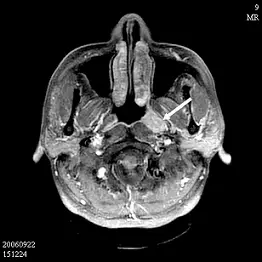

48歲男性病人主訴最近二個月左側耳鳴,根據附圖 MRI 之影像,箭號所指最恰當的診斷為何?

第一張影像(T1 加強後軸向切面)

• 左側咽鼓管咽口(torus tubarius)後上方可見一強化的軟組織腫塊,位於 fossa of Rosenmüller 區域。該處為鼻咽癌最常見發生點之一,腫塊邊緣增強明顯,與周圍正常咽壁分界清楚。

第二張影像(T2 軸向切面)

• 左側乳突骨空及中耳腔呈高信號,代表積液存在。對側無類似表現,顯示為單側中耳積液與乳突空腔積液,提示咽鼓管功能障礙或阻塞所致的 serous otitis media 及乳突腔積液(可誤以為急性乳突炎,但無膿腫或骨破壞之典型徵象)。